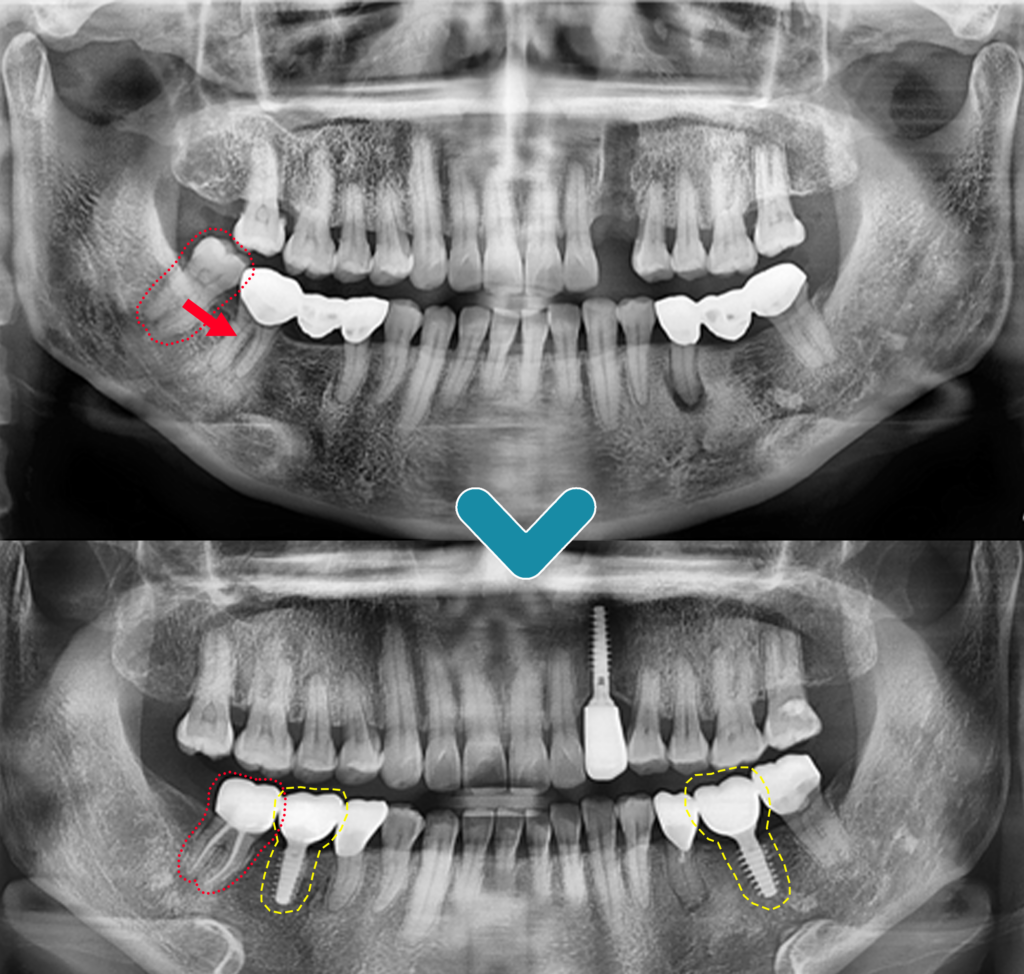

치료 전후의 모습입니다. 사랑니를 이용한 자가치아이식술로 발치 공간을 회복하였으며, 건강하게 유지가 되고 있습니다. 왼쪽과 오른쪽의 첫 번째 큰 어금니 또한 잇몸뼈와의 단단한 유착이 이루어져 성공적으로 치료가 마무리되었습니다. 자가치아재식술을 통한 회복은 자신의 치아를 이식하는 방법으로 임플란트와 비교하여 이물감이 적고, 음식물도 덜 낀다는 장점이 있습니다.전주완산구치과 프라임치과에서는 최대한 환자분을 생각하는 마음으로 치아를 살려 사용할 수 있을 경우 권해드리며, 환자분과의 충분한 상담 후 치료를 진행하고 있습니다.